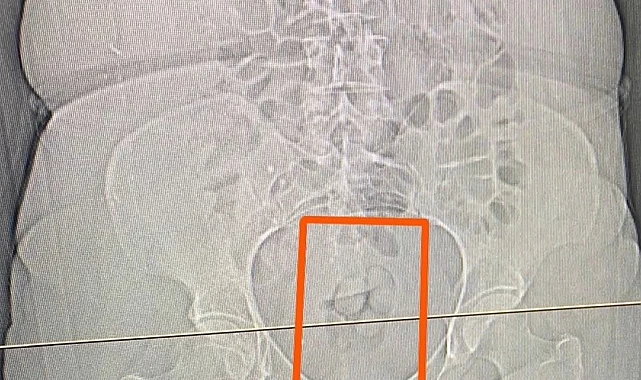

S.S. isimli şahısın şüpheli görülmesi üzerine çekilen tomografi neticesinde şahsın midesinde yabancı maddeler tespit edildi. Yapılan iç beden muayenesi sonucunda ise şahıstan 21,39 gram metamfetamin maddesi ele geçirildi.